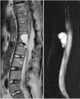

Degenerative lesion